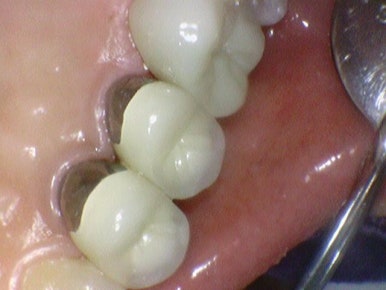

어금니 지르코니아 크라운 전후

지르코니아 크라운은?

최근 10년동안은 골드보다는 지르코니아가 대부분의 치과에서

크라운 재료로 쓰이고 있습니다.

당연히 금색인 골드 크라운과 달리

지르코리아 크라운은 색상이 자연치아처럼 하얀색이어서 눈에 띄지 않으면서

내구성도 강합니다.

또한 금값이 정말 금값인 요즘, 골드크라운보다 저렴합니다.

내구성도 강하기 때문에 굳이 골드크라운으로 할 필요가 없어서

대부분의 케이스에서 대부분의 치과에서 요즘은 크라운이 필요한 경우 지르코니아 크라운이 대세입니다.